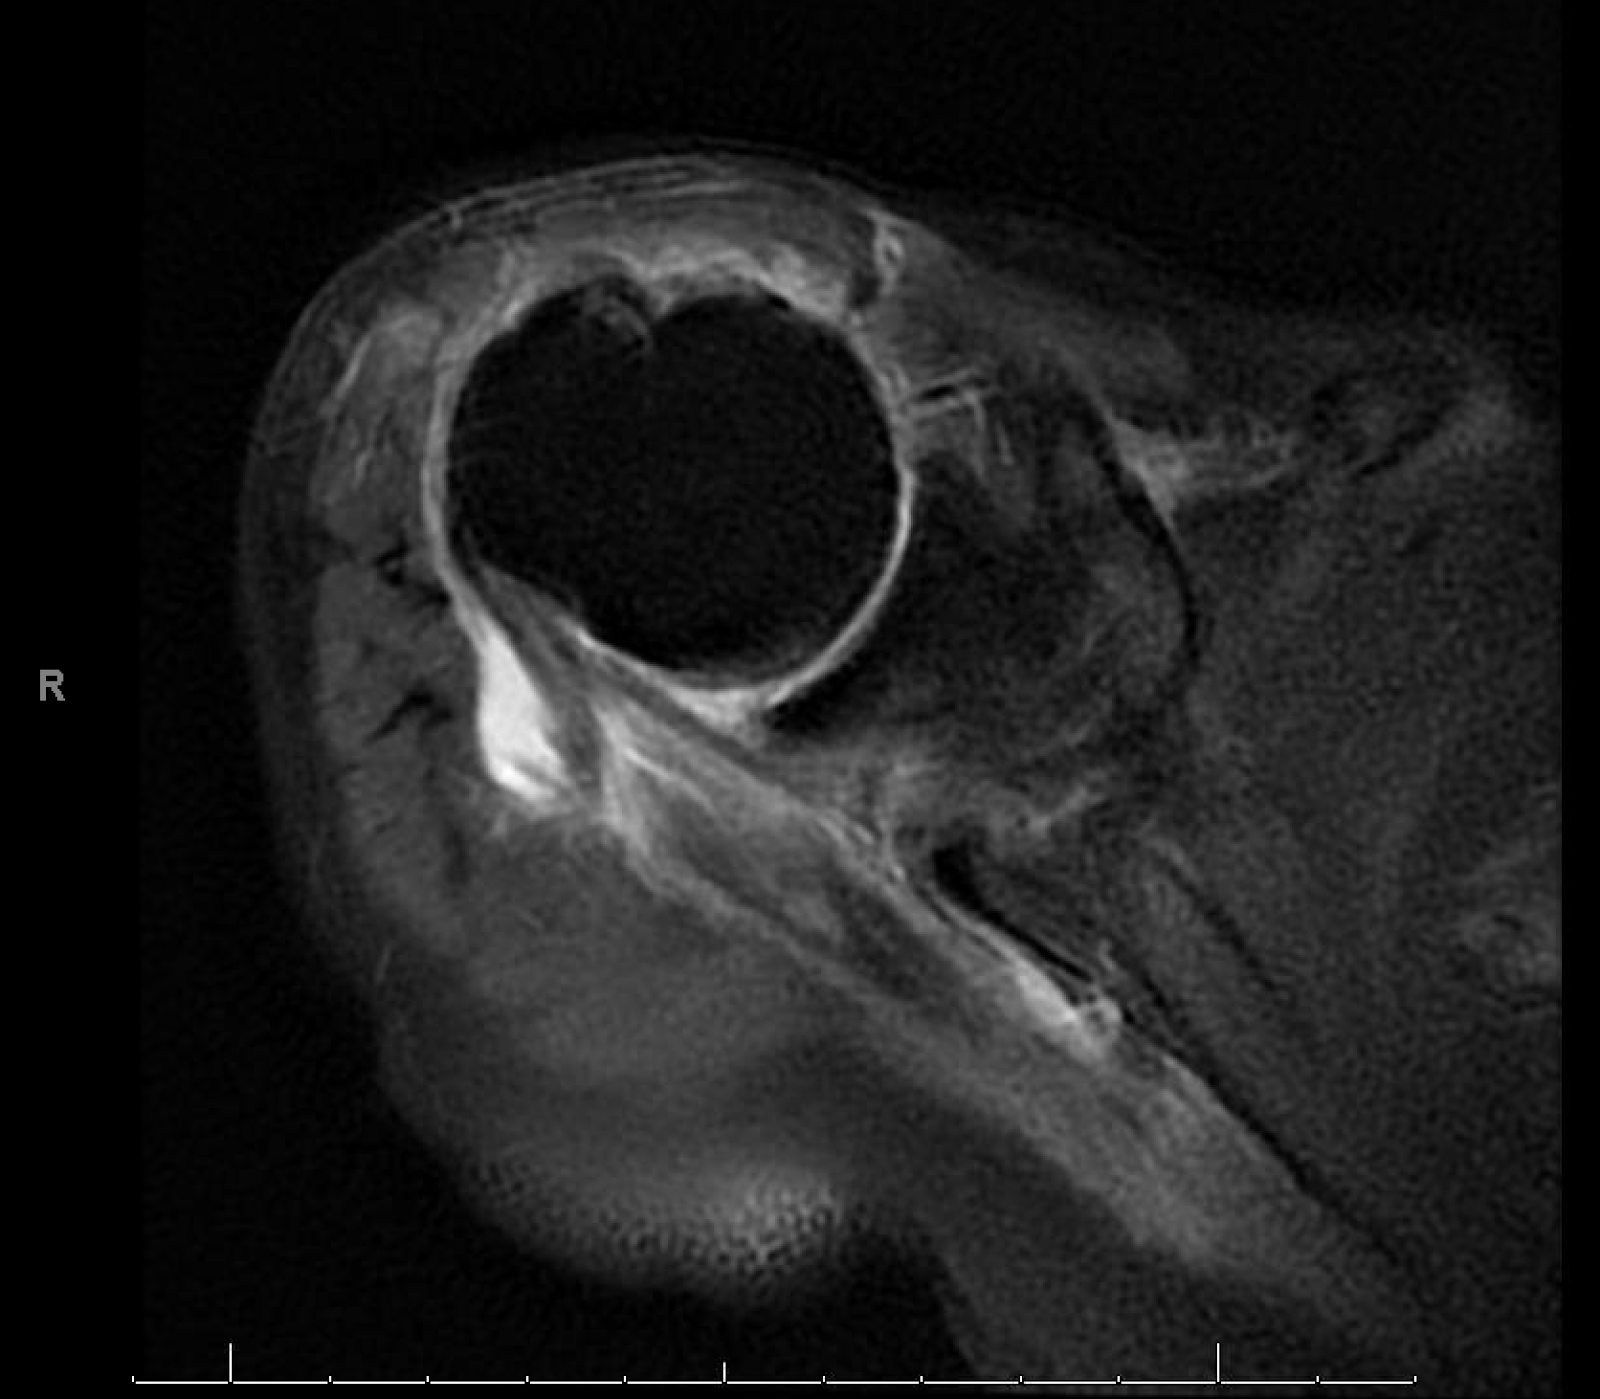

Rotator Cuff Surgery Elderly Patients . With increasing age, the prevalence of rcts also. Rotator cuff tears (rct) are a common clinical problem in the geriatric population, and debate exists over how to best provide pain relief and. Our results showed that statistically and clinically significant rom and cms recovery and a rotator cuff integrity rate of 75% can be. Rotator cuff tears (rcts) are a common cause of pain and shoulder dysfunction (1, 2). In 2004, frankle et al. Rotator cuff repair in patients aged >75 years could achieve high clinical success rates with good outcomes and pain relief. Michael stone followed 83 patients 75 years or older for five years following arthroscopic rotator cuff repair. Rotator cuff tears (rct) are a common clinical problem in the geriatric population, and debate exists over how to best provide pain relief and.